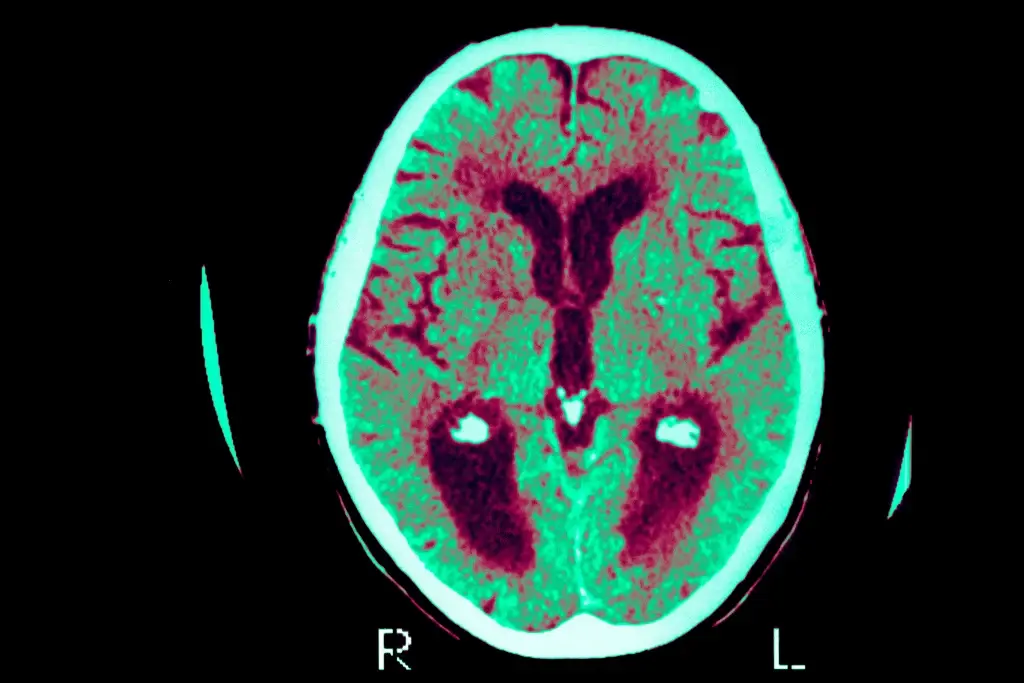

Prof. Paul Brennan drills minimal cortex holes for deep tumors, donating thumb-sized pink, pulsing samples to Dr. Claire Durrant’s team. Sliced 10-20 cells thin, kept alive in artificial CSF incubators, tissue faces Alzheimer’s proteins—revealing synapse loss mechanisms firsthand. UK sees 1M dementia cases; this rare live-adult-brain work skips animal models.